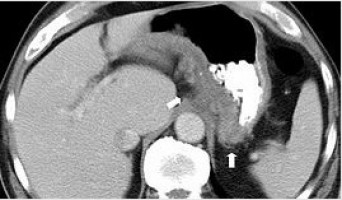

CTC works by taking hundreds of x-ray “slices” through the body which are then processed by a computer to create a ‘virtual’ 3D image of the inside of the bowel, similar to what is seen during colonoscopy. CTC is a less uncomfortable test and, unlike colonoscopy, patients do not need to be sedated.